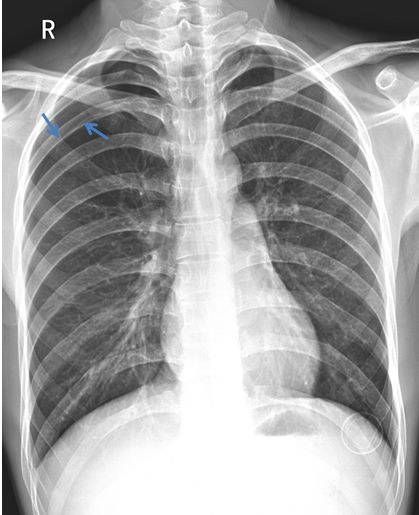

2018.4.20 经过约20天的治疗,肺组织已复张